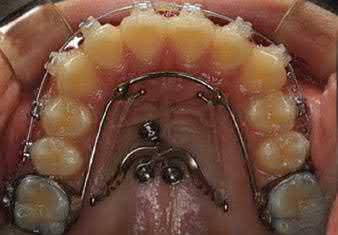

For open bite correction, TADs can be combined with a transpalatal arch (TPA) to provide efficient maxillary posterior tooth intrusion along with tongue exercise (Figure 1.6) [20]. Anterior open bite also can be corrected with TADs and miniplates (Figure 1.7) [21]. Miniplates were placed bilaterally in the zygomatic arch and the mandibular molar regions to provide absolute anchorage for bimaxillary molar intrusion. This approach can not only treat dentoskeletal open bite with positive overbite but can also achieve a counterclockwise rotation of the mandible. In lingual orthodontics, palatal

TADs can be used to retract the anterior dentition and intrude the posterior dentition to correct anterior open bite (Figure 1.8) [22]. One advantage of this modality is that the proclination and intrusion of the maxillary anterior teeth can be controlled by adjusting the length of the crimpable hooks and the vertical locations of the palatal TADs (Figure 1.8c).